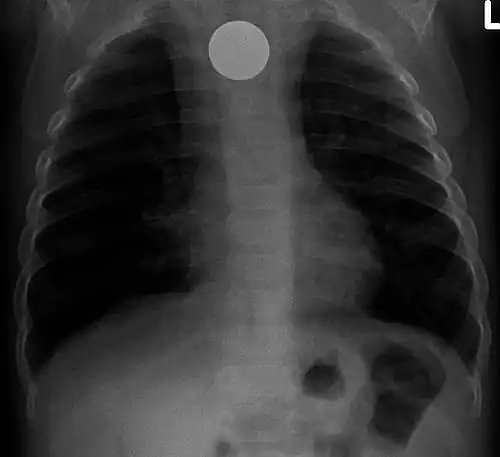

A coin seen on AP CXR in the esophagus -

A coin seen on lateral CXR in the esophagus -